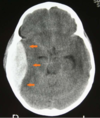

A nine-year-old boy was playing soccer when he took a blow to the side of the head. He was immediately taken to the hospital where CT scans reveal a lens shaped hematoma around the area where the frontal, parietal, temporal, and greater wing of the sphenoid join. The artery likely damaged, passes through which foramen to gain access to the cranial vault?

The point where the frontal, parietal, temporal, and greater wing of the sphenoid join is known as the pterion. Passing behind the pterion is the middle meningeal artery, which passes through foramen spinosum to access the cranial vault.

Following a car accident, a patient presents with signs of increased intracranial pressure. Radiologic studies reveal a crescent-shaped hematoma near the junction of the parietal and frontal lobes, which does not cross the midline. Which structure impedes the collection of blood from crossing the midline?

This is an example of a subdural hematoma, which is usually caused by ruptured veins that bleed into the space between the dura and arachnoid mater. The falx cerebri is an extension of the dura mater and since this hematoma is deep to the dura, it is blocked from crossing the midline by this structure. The superior sagittal sinus is contained within the falx cerebri but is not the structure directly preventing the hematoma from spreading.

Pterion

where the sphenoid, temporal, frontal, and parietal bones meet

an extremely thin region of the skull.

Weakest part of the skull. The anterior division of the middle meningeal artery runs underneath the pterion. Consequently, a traumatic blow to the pterion may rupture the middle meningeal artery causing an epidural haematoma.